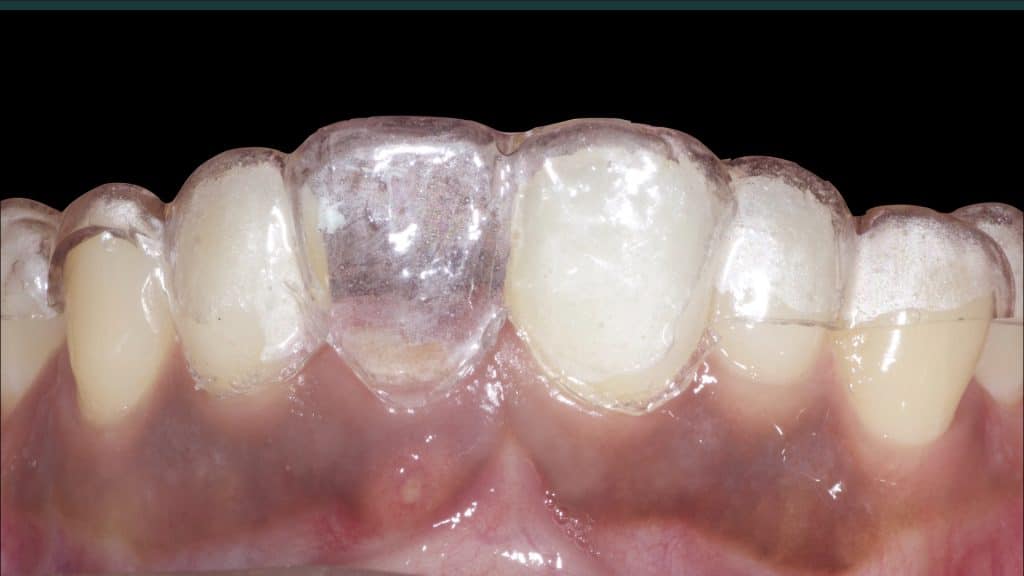

Occlusal check